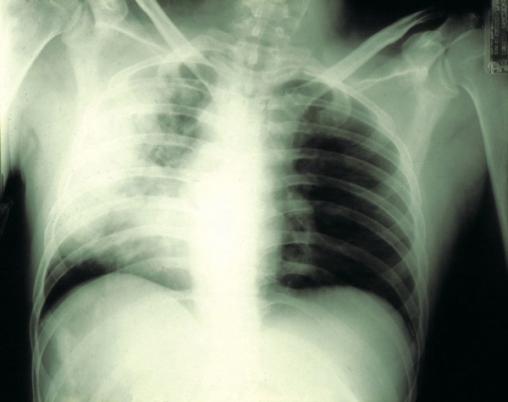

©La Revue du Praticien Radiographie de thorax de face. Opacité alvéolaire du lobe supérieur droit au cours d'une pneumonie à pneumocoque.